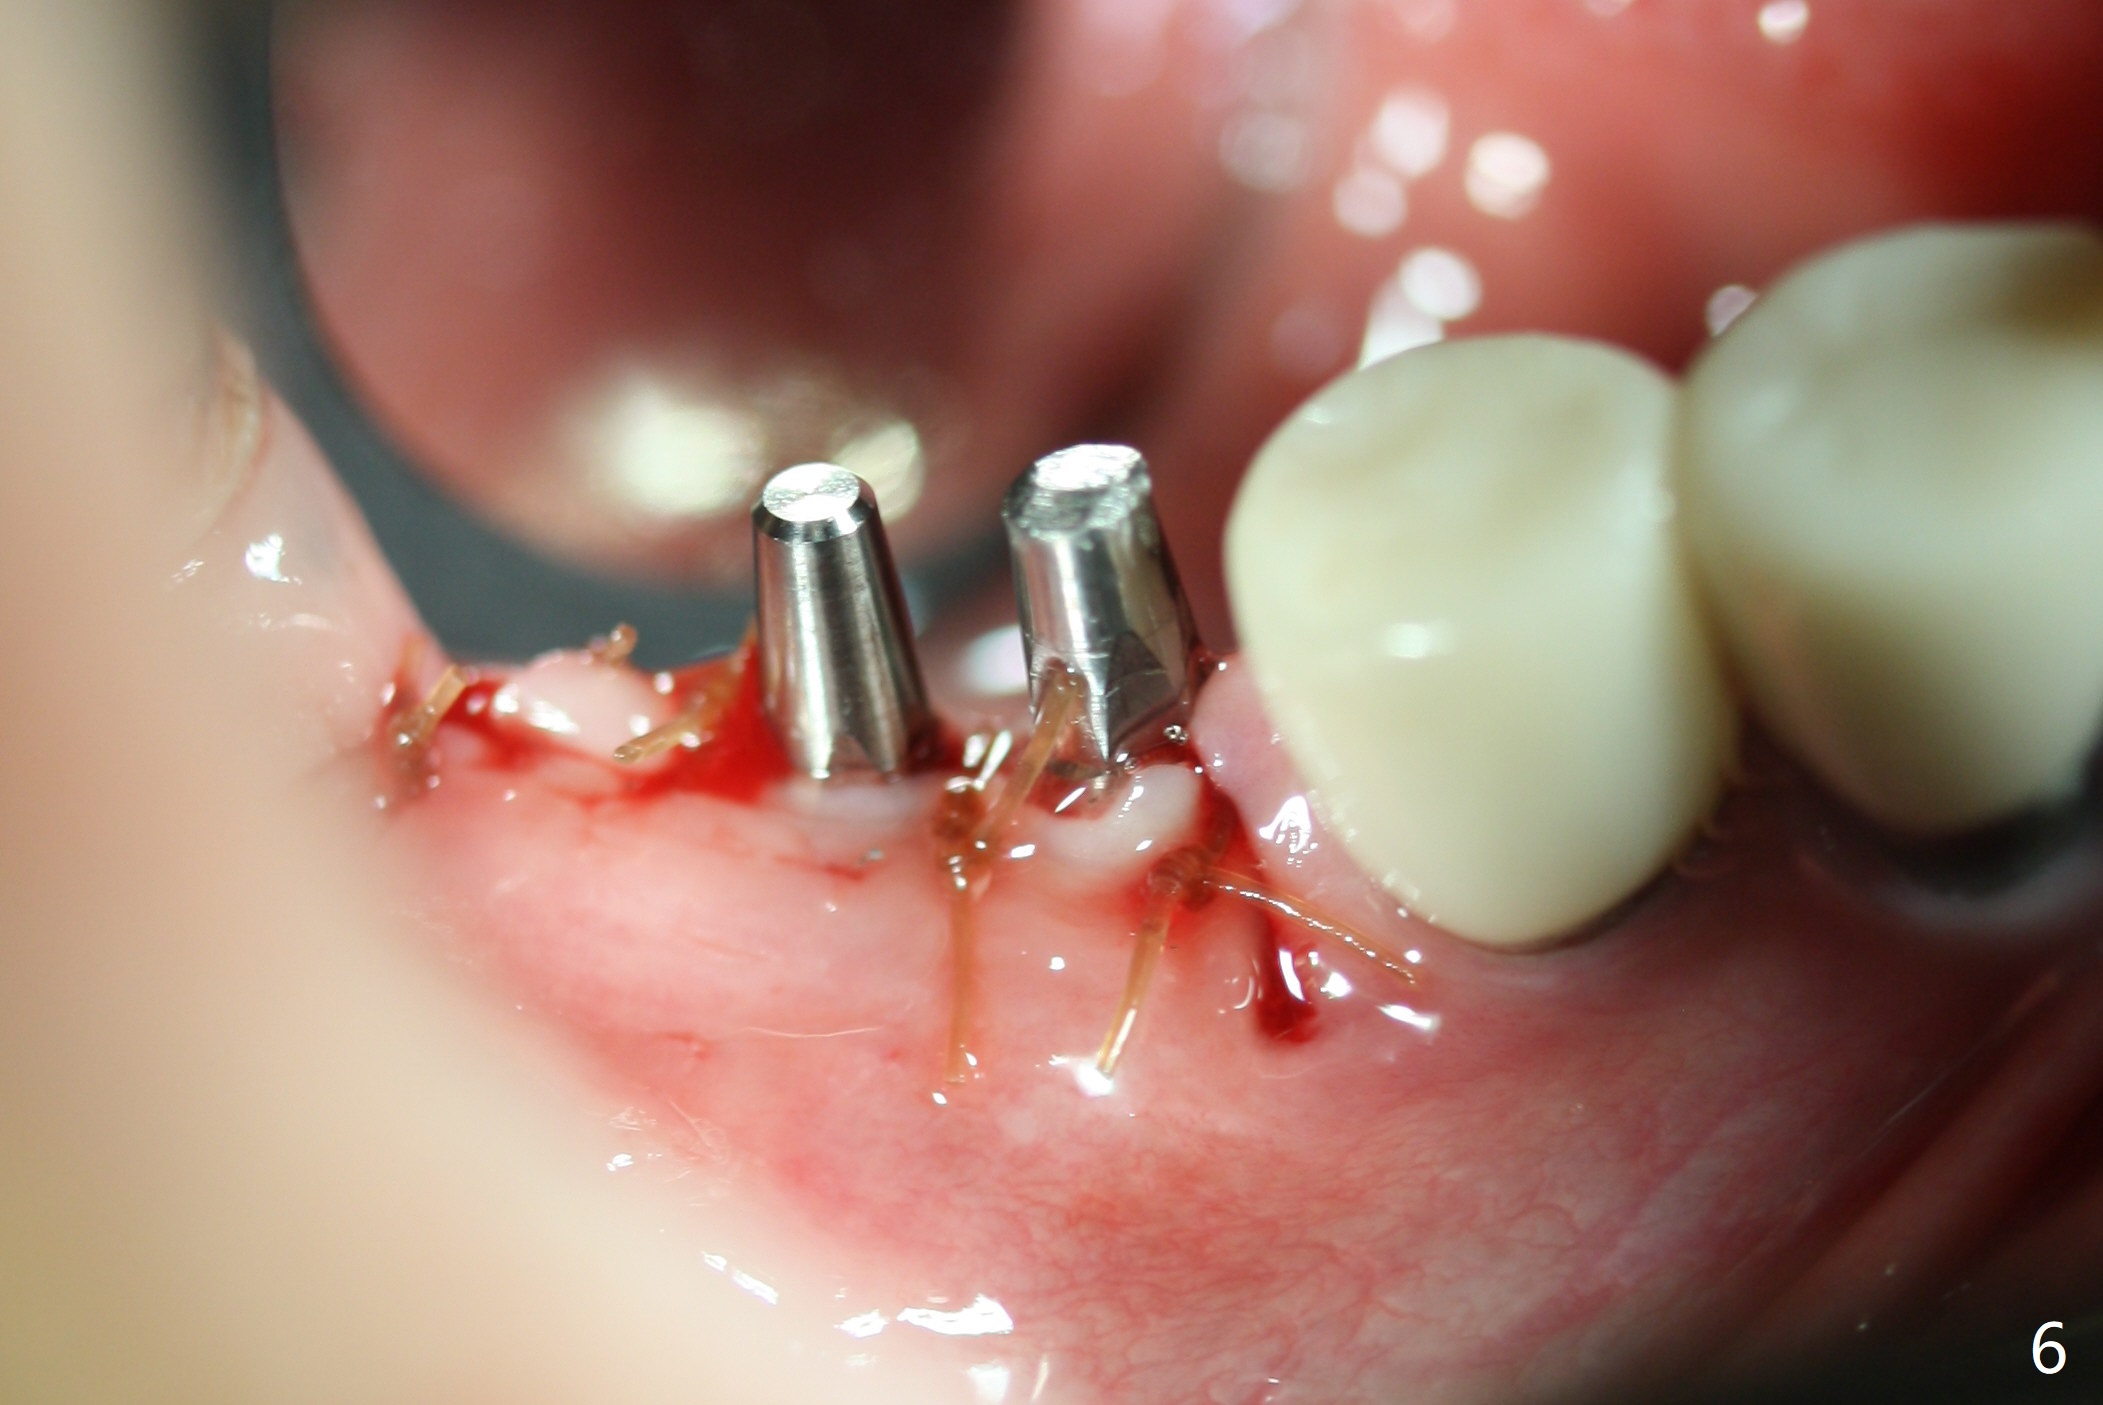

The edentulous ridge at #30 is narrow (Fig.1). After ridge reduction, osteotomy is initiated with 1.2 mm drill for 10 mm; the mesial osteotomy is to be changed (Fig.2 red line). Using a 1.2 mm drill placed in the distal osteotomy (Fig.3 D), the mesial osteotomy changes in trajectory with subsequent placement of a 2.5x10(4) mm 1-piece implant. Since the mesial implant is high in occlusion, the cuff of the distal implant is changed to be 2 mm (Fig.4 (shorter black line)). Panoramic X-ray is taken to show no violation of the Inferior Alveolar Canal (Fig.5 red dashed line). These two 1-piece implants are slightly lingually placed (Fig.6). The crestal bone around the implants resorbs without thread exposure 5 months postop (Fig.7). Impression is taken for a splinted crown (Fig.8-12). There is no metal show around the 2.5 mm 1-piece implants 6 months postop (advantage) vs. that at #28 and 29 (Fig.13). Bitewing is taken post cementation to determine whether residual cement is present (Fig.14). There is periodic swelling and pain in the lower right quadrant 2 years post cementation (Fig.15). In fact periimplantitis appears to have developed at #28 (Fig.16) with loss of the buccal bone (Fig.17,18). The buccal bone loss is less at #29 (Fig.19) and #20 (Fig.23) and no at #30 mesial and distal implants (Fig.20,21). A much smaller implant will be placed lingually at #28 immediate (Fig.24,25).